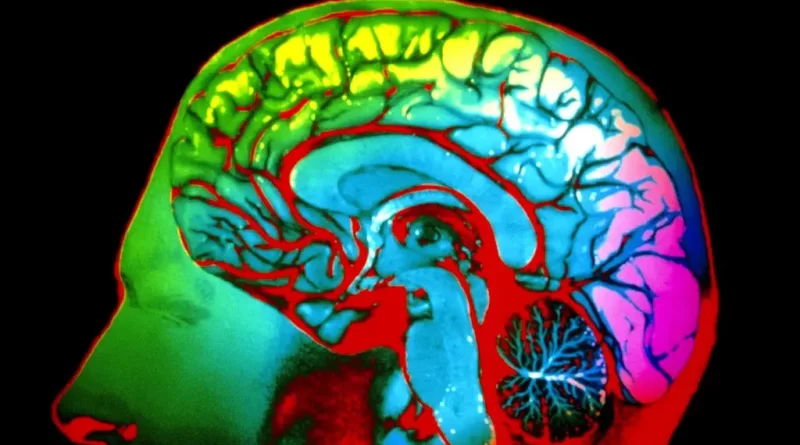

But scientists do have a good understanding of which parts of the brain handle vision. They have even figured out where various vision-processing tasks are performed, like recognizing what is moving, identifying colors and adjusting to different lighting conditions.

Amazingly, it is even possible to deduce what you’re seeing by looking at an M.R.I. scan showing which parts of your brain are lighting up.

That is, researchers pulled off this sleight of science with individuals. They would first show a subject lying in the M.R.I. machine a series of images, mapping out how that person’s brain responded. After that initial training, the researchers could randomly show one of the images and, based on just the brain activity, make a good guess at what the image was.

In new research, Dr. Bartels and Michael Bannert, a postdoctoral researcher in Dr. Bartels’ laboratory, used that technique to provide a partial answer to the question of whether most of us have a shared sense of colors. They put 15 people, all with standard color vision, in an M.R.I. machine. The volunteers viewed expanding concentric rings that were red, green or yellow.

They used data from 45 subjects to calculate an average color-induced response in different parts of the brain. This average brain response was then used to reliably predict the color and brightness of what the 15th person was looking at.